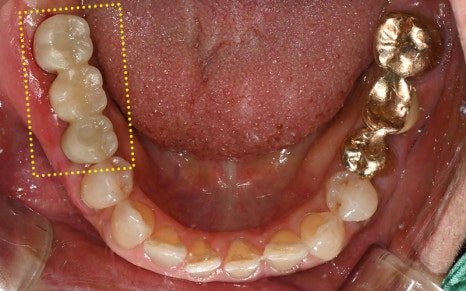

최종적으로 크라운(보철물)까지 올려

치료를 성공적으로 마무리 해드렸답니다!

💕 전 > 후 💕

2025.02.13 ㅡ> 2025.06.11